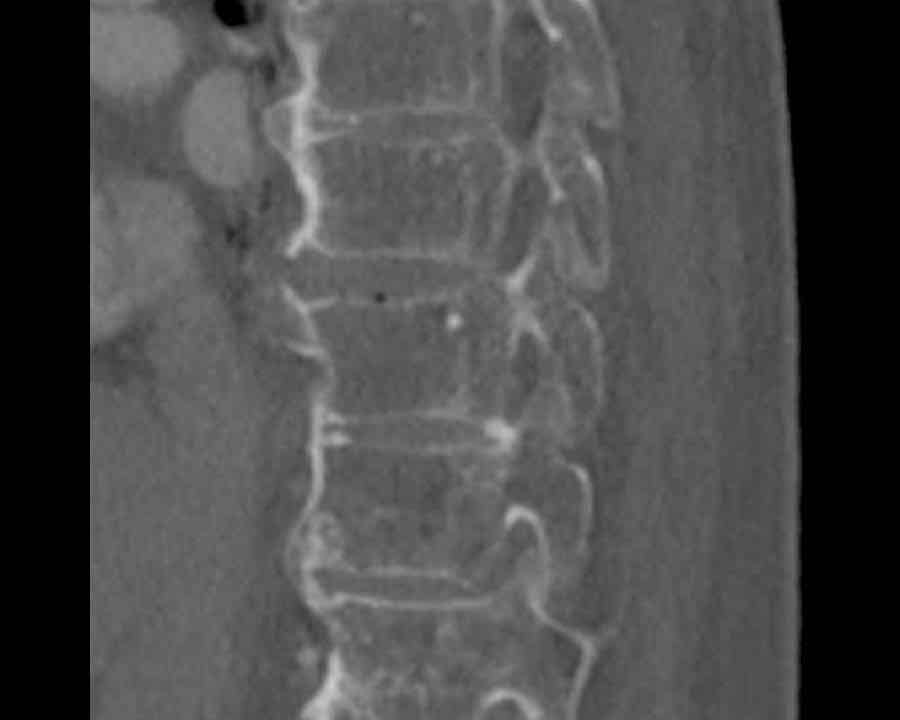

Scroll through images.

What are the findings?

Findings

- C injury? No.

- Signs of a rigid spine?

Yes, clear example of SpA so be aware of a B3 injury. - Horizontal fracture of vertebral body (white circle)

- Subtle separation anteriorly at the fracture level

Conclusion

injury type B3.